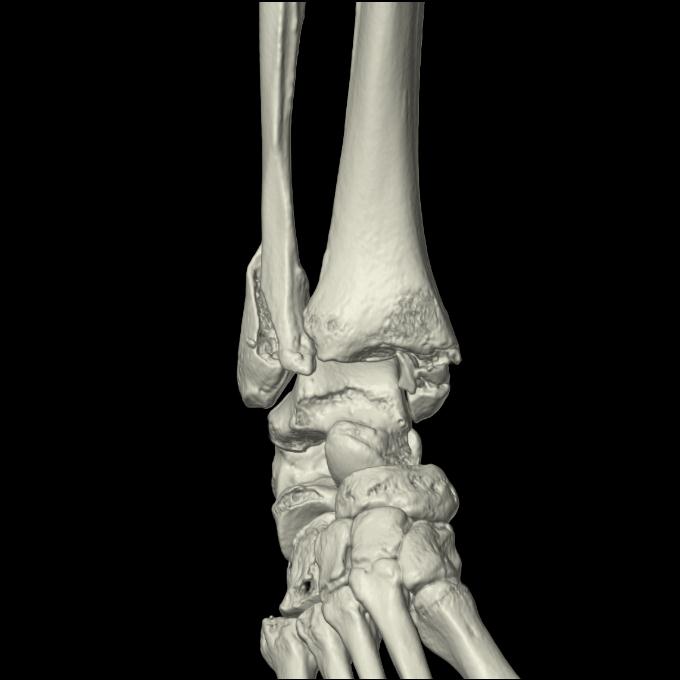

102755 1/4 2R 1/15 2R 右足関節 68歳女性 右三果脱臼骨折